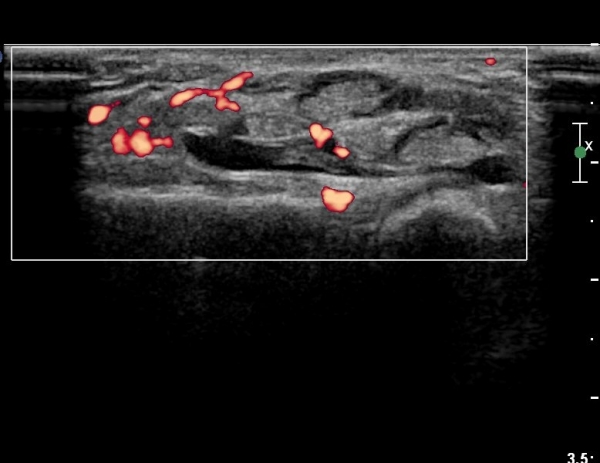

¼Õ¸ñ°ú ¼ö±Ù°ü±ÙÀ§ºÎ Ⱦ´Ü¸é°Ë»ç¿¡¼­  ÈûÁÙÀÇ ºñÈÄ¿Í ÈûÁÙ ÁÖÀ§ Ȱ¾×¸· ºñÈİ¡ °üÂûµÇ³ª

Á¤Áß½Å°æ ºÎÁ¾Àº °üÂûµÇÁö ¾Ê´Â´Ù(»çÁø 3, 4).